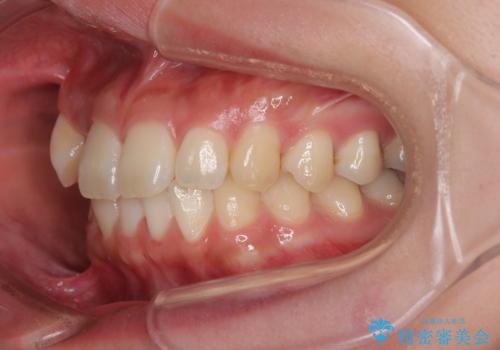

- 上下前歯のデコボコを気にして来院された患者様です。

ワイヤー矯正でもマウスピース矯正でも可能でしたが、短期間で、自身の手を煩わせることなく治療を行いたいとのことで、ワイヤー装置にて矯正治療を行うこととしました。

僅か8ヶ月という短期間で、綺麗な歯列に仕上がりました。